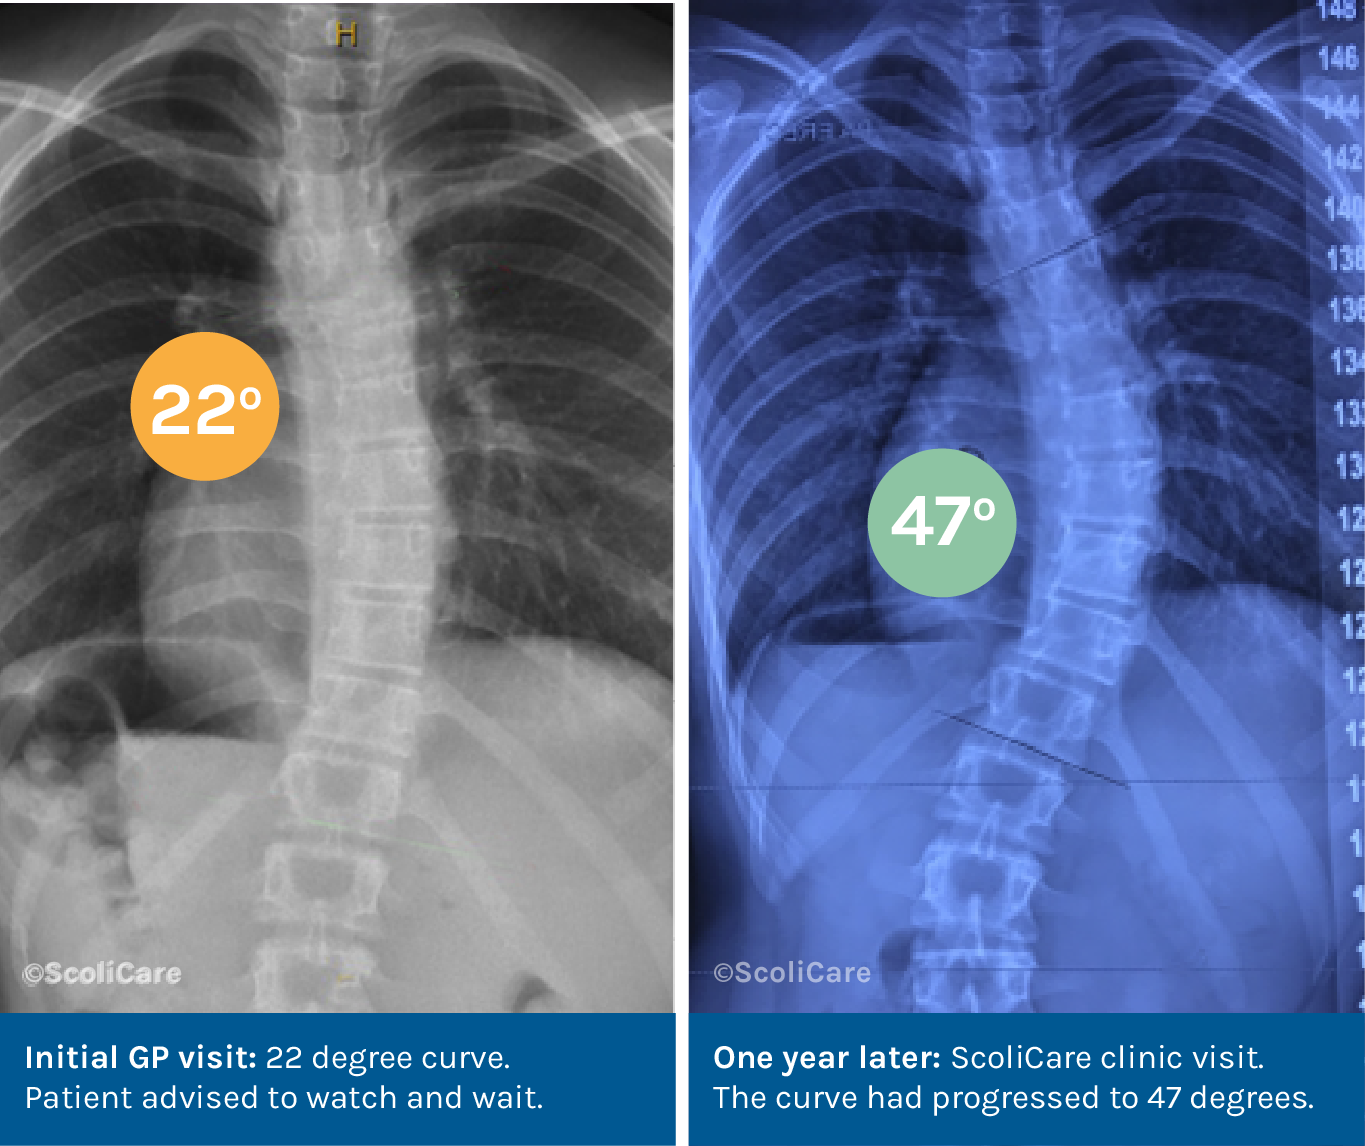

The Risks of the Watch and Wait Approach

Early scoliosis treatment is crucial to prevent curve progression and avoid severe deformities or health issues.

The ‘watch and wait’ approach – often recommended for mild cases – may not be suitable as scoliosis can worsen rapidly during growth spurts, particularly in adolescents. And delaying treatment can result in the need for more invasive procedures later on.

ScoliCare recommend early assessment and proactive management to ensure optimal outcomes and prevent long-term health problems.